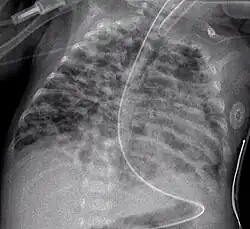

![]() Obraz radiologiczny dysplazji oskrzelowo-płucnej. | |

Charakteryzuje się koniecznością przewlekłej tlenoterapii powyżej 28 dnia życia i charakterystycznym obrazem RTG płuc. Jest też określana jako dysplazja oskrzelowo-płucna.